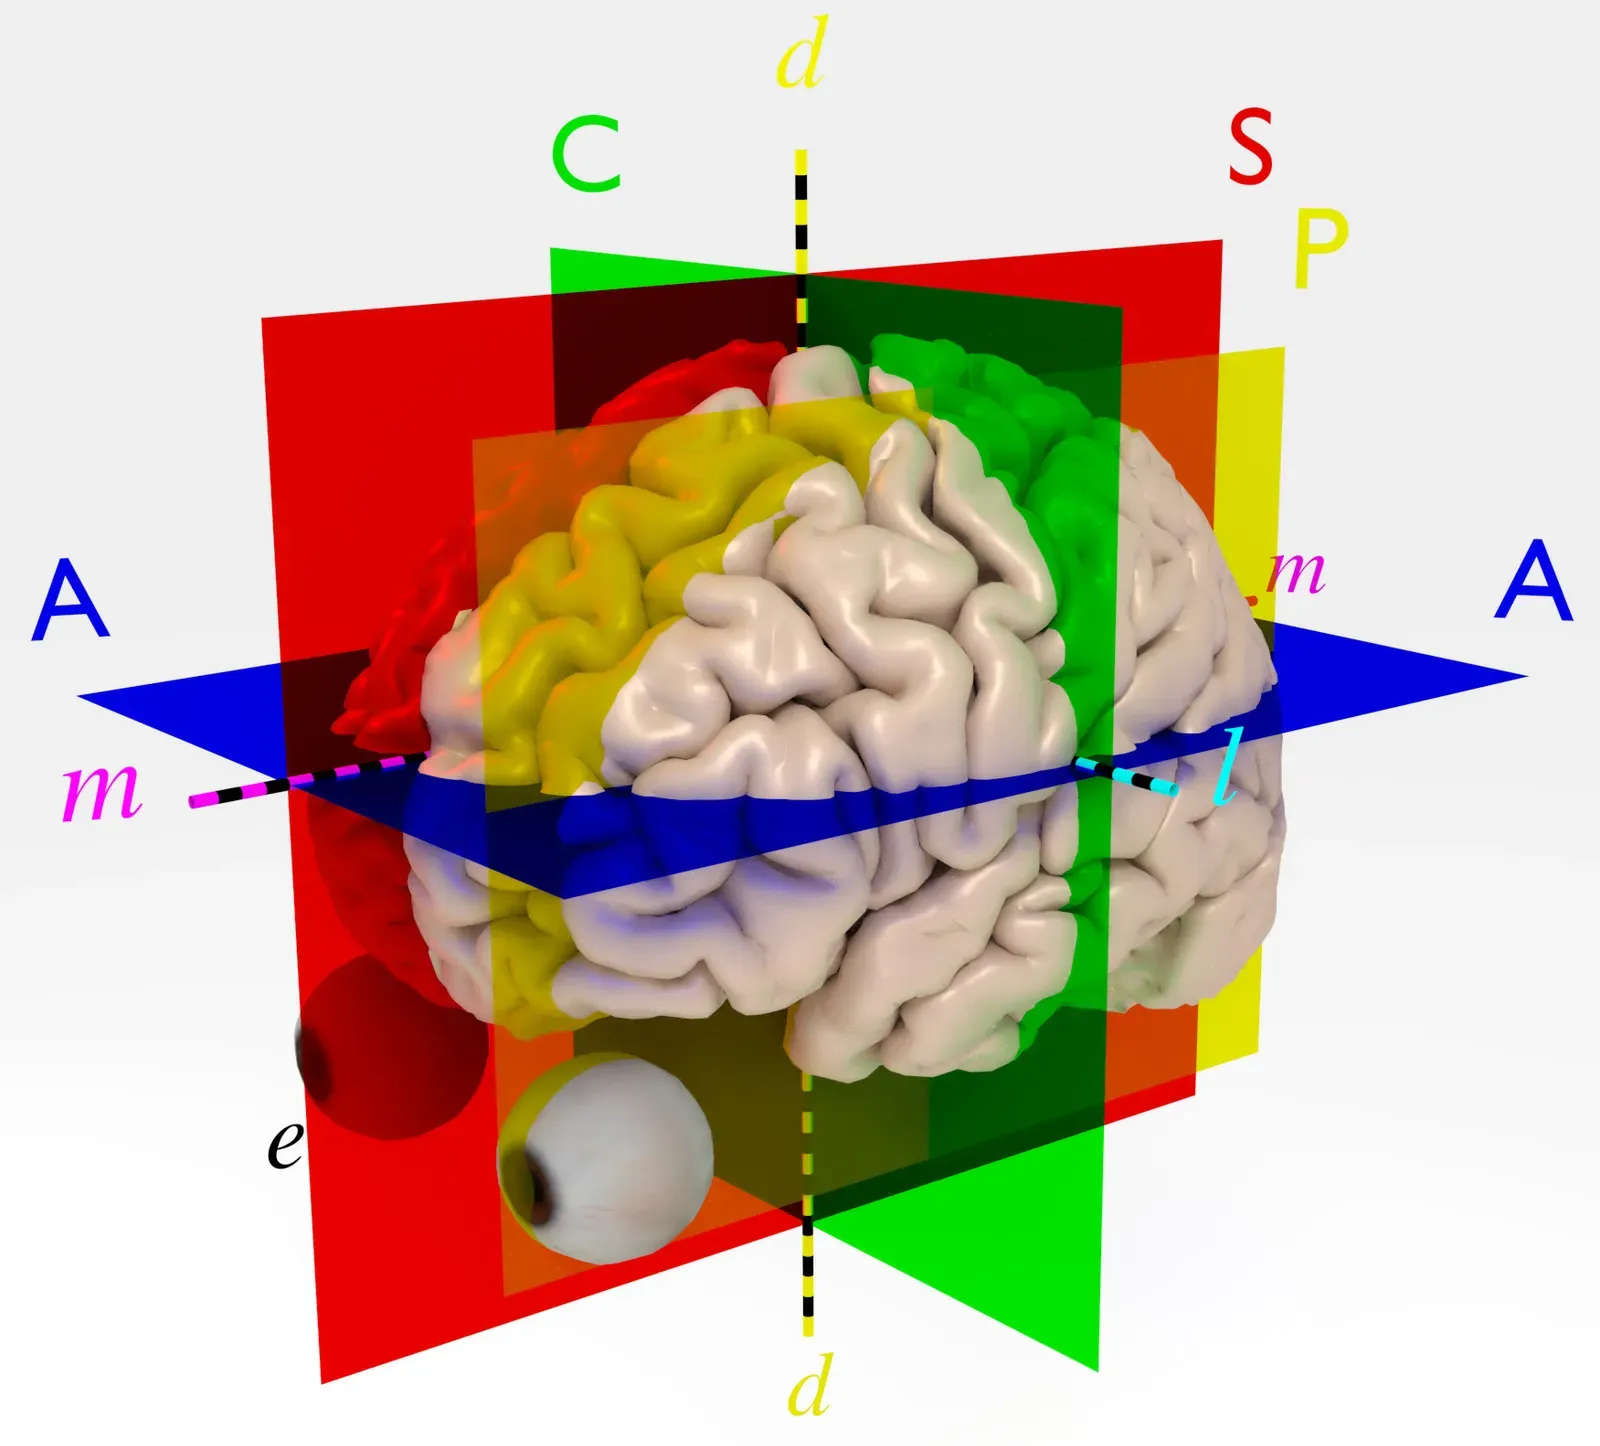

Your brain is already a master of integration, constantly blending information from your eyes, ears, skin, and inner body to create a single, seamless world. In synesthesia, researchers think some of that integration goes further than usual, likely because of extra connections or unusual communication between specific brain regions. For example, when you see letters and numbers as colors, the area that processes shapes and symbols is believed to “talk” more directly with the area that processes color, so the two experiences fuse together automatically.

Scientists also use brain imaging and clever reaction‑time experiments to peek under the hood. When you experience synesthetic colors or spatial layouts, your brain often activates regions that match those added sensations more strongly than in people without synesthesia. In speeded tasks, your performance can be helped or hindered by your synesthetic associations, which shows they are not just decorative ideas floating in the background. Together, these methods reveal that synesthesia behaves like a genuine perceptual feature of your mind, not a passing whim or a trick of language.